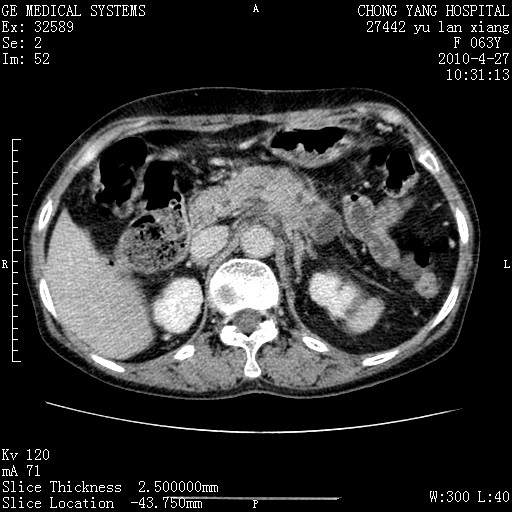

标题: CT26066:F63Y 上腹正中压痛半月,CA199:7400u/ml,MR示胰腺炎伴 [打印本页]

胰腺癌侵犯腹腔动脉干-分支、胃壁、左侧膈肌伴胰周及腹膜后淋巴结转移、胆囊切除术后。

胰腺癌侵犯腹腔动脉干-分支、胃壁、左侧膈肌伴胰周及腹膜后淋巴结转移、胆囊未显影。